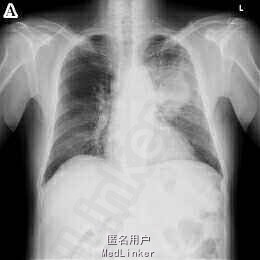

67岁男性,因进行性气促和体重下降2月于前来就诊。

胸部CT提示左肺巨大肿物(图A),痰液细胞学检查示腺癌阳性。另外,患者诉双下肢疼痛,X线检查显示右股骨可见骨膜反应(图B)。骨闪烁显像示双侧股骨及胫骨弥漫皮质摄取(图C),符合肺性肥大性骨关节病(HPOA)。